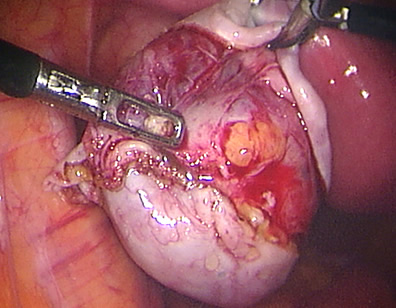

The products of conception are removed completely from the tube.

The tube was closed back and reconstructed. If a pregnancy ectopic is suspected early, laparoscopic surgery may help to preserve the tube involved.